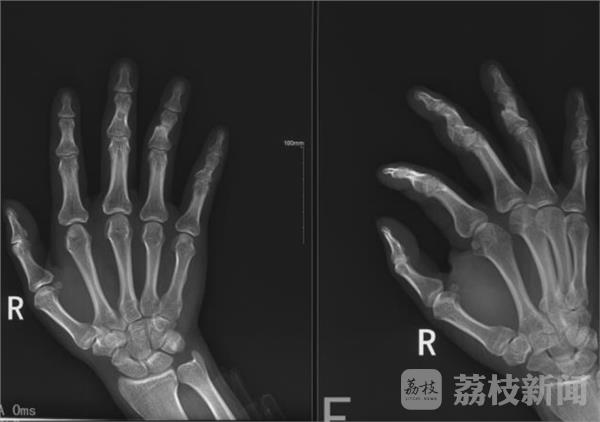

1月24日,荔枝新闻记者从盐城市盐都警方获悉,近日该市打掉了一个流窜江苏、浙江、安徽三省的“碰瓷”诈骗团伙,四名犯罪嫌疑人被抓获。据介绍,“碰瓷”团伙一名成员为了诈骗,拿砖头石块砸伤自己手指,或用手指敲击硬物直至骨折,一双手有五个指头有陈旧性骨折。“这些陈旧性骨折也显示他作案很多次。”办案民警说。

医院的X光片表明,王某的手指确实骨折了,张某只得自认倒霉赔偿5000元钱。“赔”完钱回到家后,张某越想越不对劲,自己好好的开电瓶三轮车,怎么就碰到人了?真碰到人的话怎么就骨折了?真骨折的话对方怎么就轻易私了了?张某感觉自己可能是被人“下套”了,当天下午便到派出所报了警。